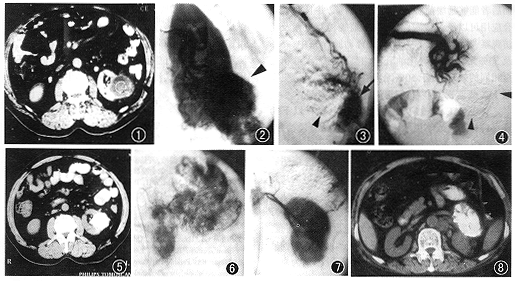

TAE后即刻血管造影显示为部分(7例)肾切除及全部肾上腺(2例)切除表现,栓塞部位碘化油聚集(图1~8)。3周后行CT扫描检查,显示肿瘤缩小,病灶内碘化油聚集。4周后所有病人重复血管造影检查未见肿瘤血管显示(图1~8)。

图1~5 为同一病人(例4),病理诊断为肾透明细胞癌。图1为CT平扫,示左肾下极占位病变;图2为血管造影,示左肾下极肿瘤染色灶(▲);图3为肾被膜动脉造影,示该血管向肿瘤供血(↓);图4为栓塞肾动脉分支及肾被膜动脉后血管造影,示肿瘤血供完全消失(▲),4周后重复血管造影显示同样结果;图5为3周后CT平扫示肿瘤缩小,碘化油在病灶内均匀聚集 图6~8 为同一病人(例8),影像诊断为左肾上腺癌。图6为肾上腺动脉造影,示左侧肾上腺区肿瘤染色灶;图7为栓塞该动脉后血管造影,示肿瘤血供消失,局部碘化油聚集;图8为3周后CT扫描,示肿瘤内碘化油聚集附表 9例肾癌、肾上腺癌病人资料及TAE后随访情况